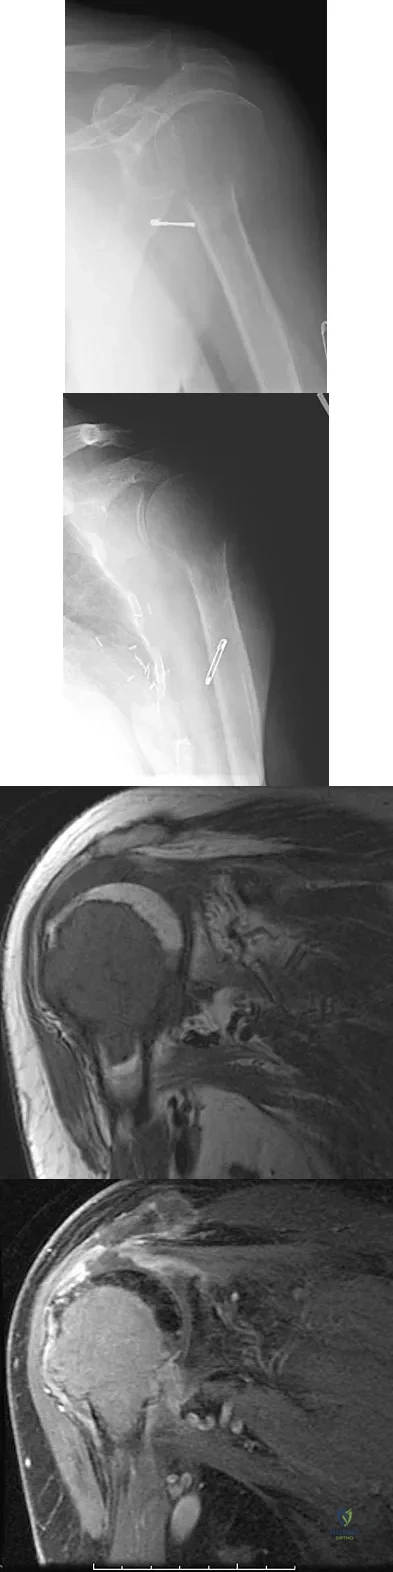

A 75-year-old woman has had severe shoulder pain for the past month. Her medical history includes hypertension and a total nephrectomy for renal cell carcinoma 7 years ago. Radiographs and sagittal MRI scans are shown in Figures 36a through 36d. A bone scan reveals this to be an isolated lesion. Biopsy findings are consistent with metastatic renal cell carcinoma. What is the most appropriate treatment for this patient?

Explanation